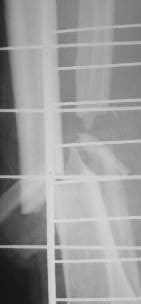

Решил использовать методику резиновой стяжки для закрытия дефекта. Рану разделил на две части . Одну часть стягивал с помощью скобок. Изготовил скобки из спиц 2мм. Скобками зацепил края раны, к скобкам привязал резиновые стяжки, которые фиксировал на деталях аппарата. Рана закрылась в течение 4х дней. Наложил вторичные швы.

Другую часть стягивал с помощью П-образных швов через резиновые трубки. В течение суток П-образные швы снял из-за угрозы прогрессирования некроза. На 4 день начал стягивать этот участок раны с помощью скобок и резиновой стяжки. Рана закрылась через 3 дня, наложил вторичные швы на этот участок. Метод понравился. Возникли вопросы.

Мы используем независимо от размера раны, а резина обычная, которая используется для сосудов как держалка, не могу точно сказать насчет натяжения, создает постоянное натяжение за край раны и сближая, уменьшает общую поверхность в течение 2-3 дней, что облегчает закрытие раны после вторичной обработки.

Для скрепления резины по краям кожи пользуемся Staples (скобы) для ушивания кожи, в Вашем случае можно провести спицы, близко по краям раны, для равномерного натяжения поверхности, с отдельными петлями через каждые 3 см для резиновой тяги.